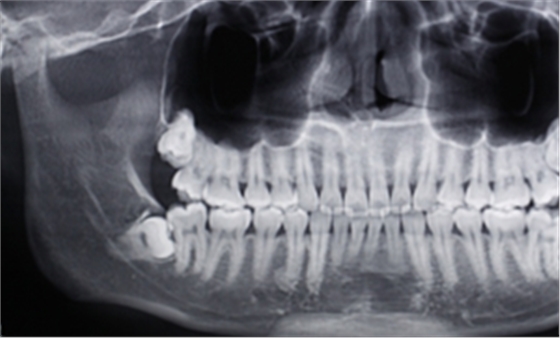

右下智齒去骨范圍如何?分冠線如何?怎樣才能最快時(shí)間能把這顆牙拔出來?

阻生牙的阻力分析及去除阻力的方法問題一:這顆智齒去骨范圍如何?分冠線如何?

答:本x線片示48近中低位埋伏阻生,且牙根緊鄰下牙槽神經(jīng)管,拔除時(shí)需注意充分去除近中方向的牙體冠方阻力及遠(yuǎn)中的牙槽骨阻力,挺出牙根時(shí)盡量做到一次完成,減少牙根與神經(jīng)管的摩擦,降低神經(jīng)受損風(fēng)險(xiǎn)。

遠(yuǎn)中:骨阻力 近中:牙體冠方組織

第一:確定阻力去骨的范圍: